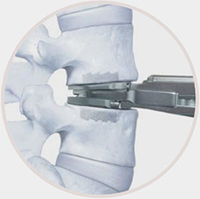

Safe and Reproducible Surgical Technique

Working with leading spine surgeons from around the world, the prodisc L instrumentation and surgical technique has been refined to facilitate safe and reproducible implantation through a midline, mini-open anterior approach to the lumbar spine.

• Three step implantation technique • Enables accurate sizing and precise placement of the implant

1. Trial

2. Chisel

3. Implant

4. Final